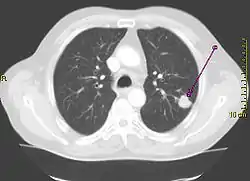

| نمونهای از تومور موجود در ریه که توسط پیکانی بر روی رادیوگرافی قفسه سینه نشان داده شدهاست. | |

انجام یک رادیوگرافی قفسه سینه یکی از نخستین مراحل تحقیقی است که باید در صورت گزارش نشانههایی توسط فرد که ممکن است دال بر سرطان ریه باشد، صورت پذیرد. این کار میتواند یک توده مشخص، گشادگی میانسینه (که میتواند بیانگر گشادگی غدد لنفاوی واقع در آنجا باشد)، آتلکتازی (جمع شدن ریه)، التهاب ریه، یا ترشح پرده جنبی را آشکار نماید.[2] تصویربرداری سیتی نوعاً به منظور ارائه اطلاعات بیشتر در مورد نوع و درجهٔ بیماری مورد استفاده قرار میگیرد. نایژهبینی یا بافتبرداری هدایت شده توسط سیتی اغلب برای نمونهبرداری تومور برای بافتآسیبشناسی مورد استفاده قرار میگیرد.[10]

سرطان ریه اغلب به صورت یک توده ریوی منزوی بر روی یک پرتونگاری قفسه سینه ظاهر میشود. لیکن تشخیص افتراقی آن بسیار گستردهاست. بسیاری از بیماریهای دیگر نظیر سل، عفونتهای قارچی، سرطان دگردیس، یا التهاب سازماندهنده ریه نیز میتوانند چنین نمودی را نتیجه دهند. از جمله علل کمتر رایج «توده ریوی منزوی» میتوان به هامارتومها، کیستهای برونکوژنیکها، ورمهای غدهای، ناهنجاری شریانی و وریدی، انزوای ریوی، تودههای روماتیسمی، گرانولوماتوز وگنر یا لنفوم اشاره نمود.[43] سرطان ریه همچنین میتواند یک یافتن تصادفی باشد که به صورت یک توده ریوی منزوی بر روی یک پرتونگاری قفسه سینه یا سیتی اسکن انجام شده بنا بر یک دلیل ناشناخته ظاهر میگردد.[44] تشخیص قطعی سرطان ریه بر پایه یک بررسی بر پایهٔ بافتشناسی بافت مورد ظن از نظر ویژگیهای بالینی و ویژگیهای وابسته به پرتونگاری میباشد.[1]